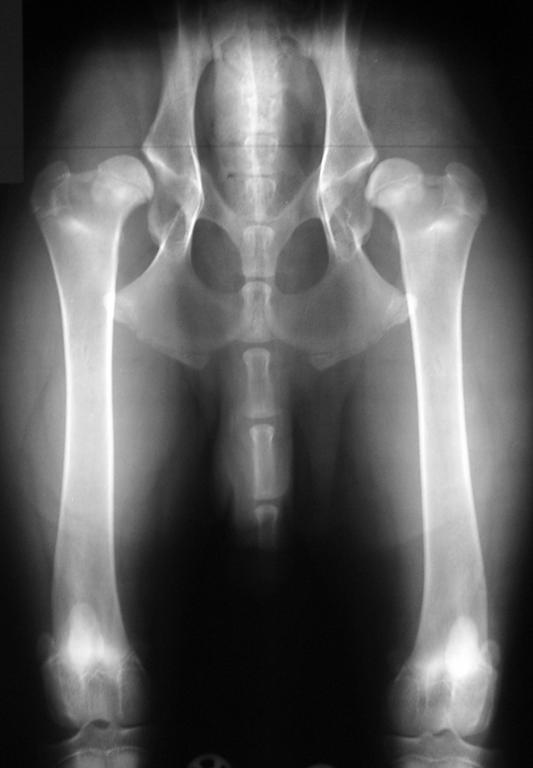

Hüftgelenksdysplasie beim Hund

- ist die häufigste erbliche orthopädische Erkrankung beim Hund

- führt zur Hüftgelenksarthrose, Schmerzen, Gelenkversteifung und zu guter Letzt zur Beeinträchtigung der Lebensqualität

- betrifft bei manchen Rassen mehr als 50% aller Hunde